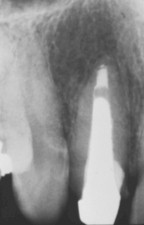

Fig. 10 RX

mesioradial de prueba antes de la cementación de un poste colado paralelo.

Nótese la diferencia en el diámetro cervical y apical del conducto. |